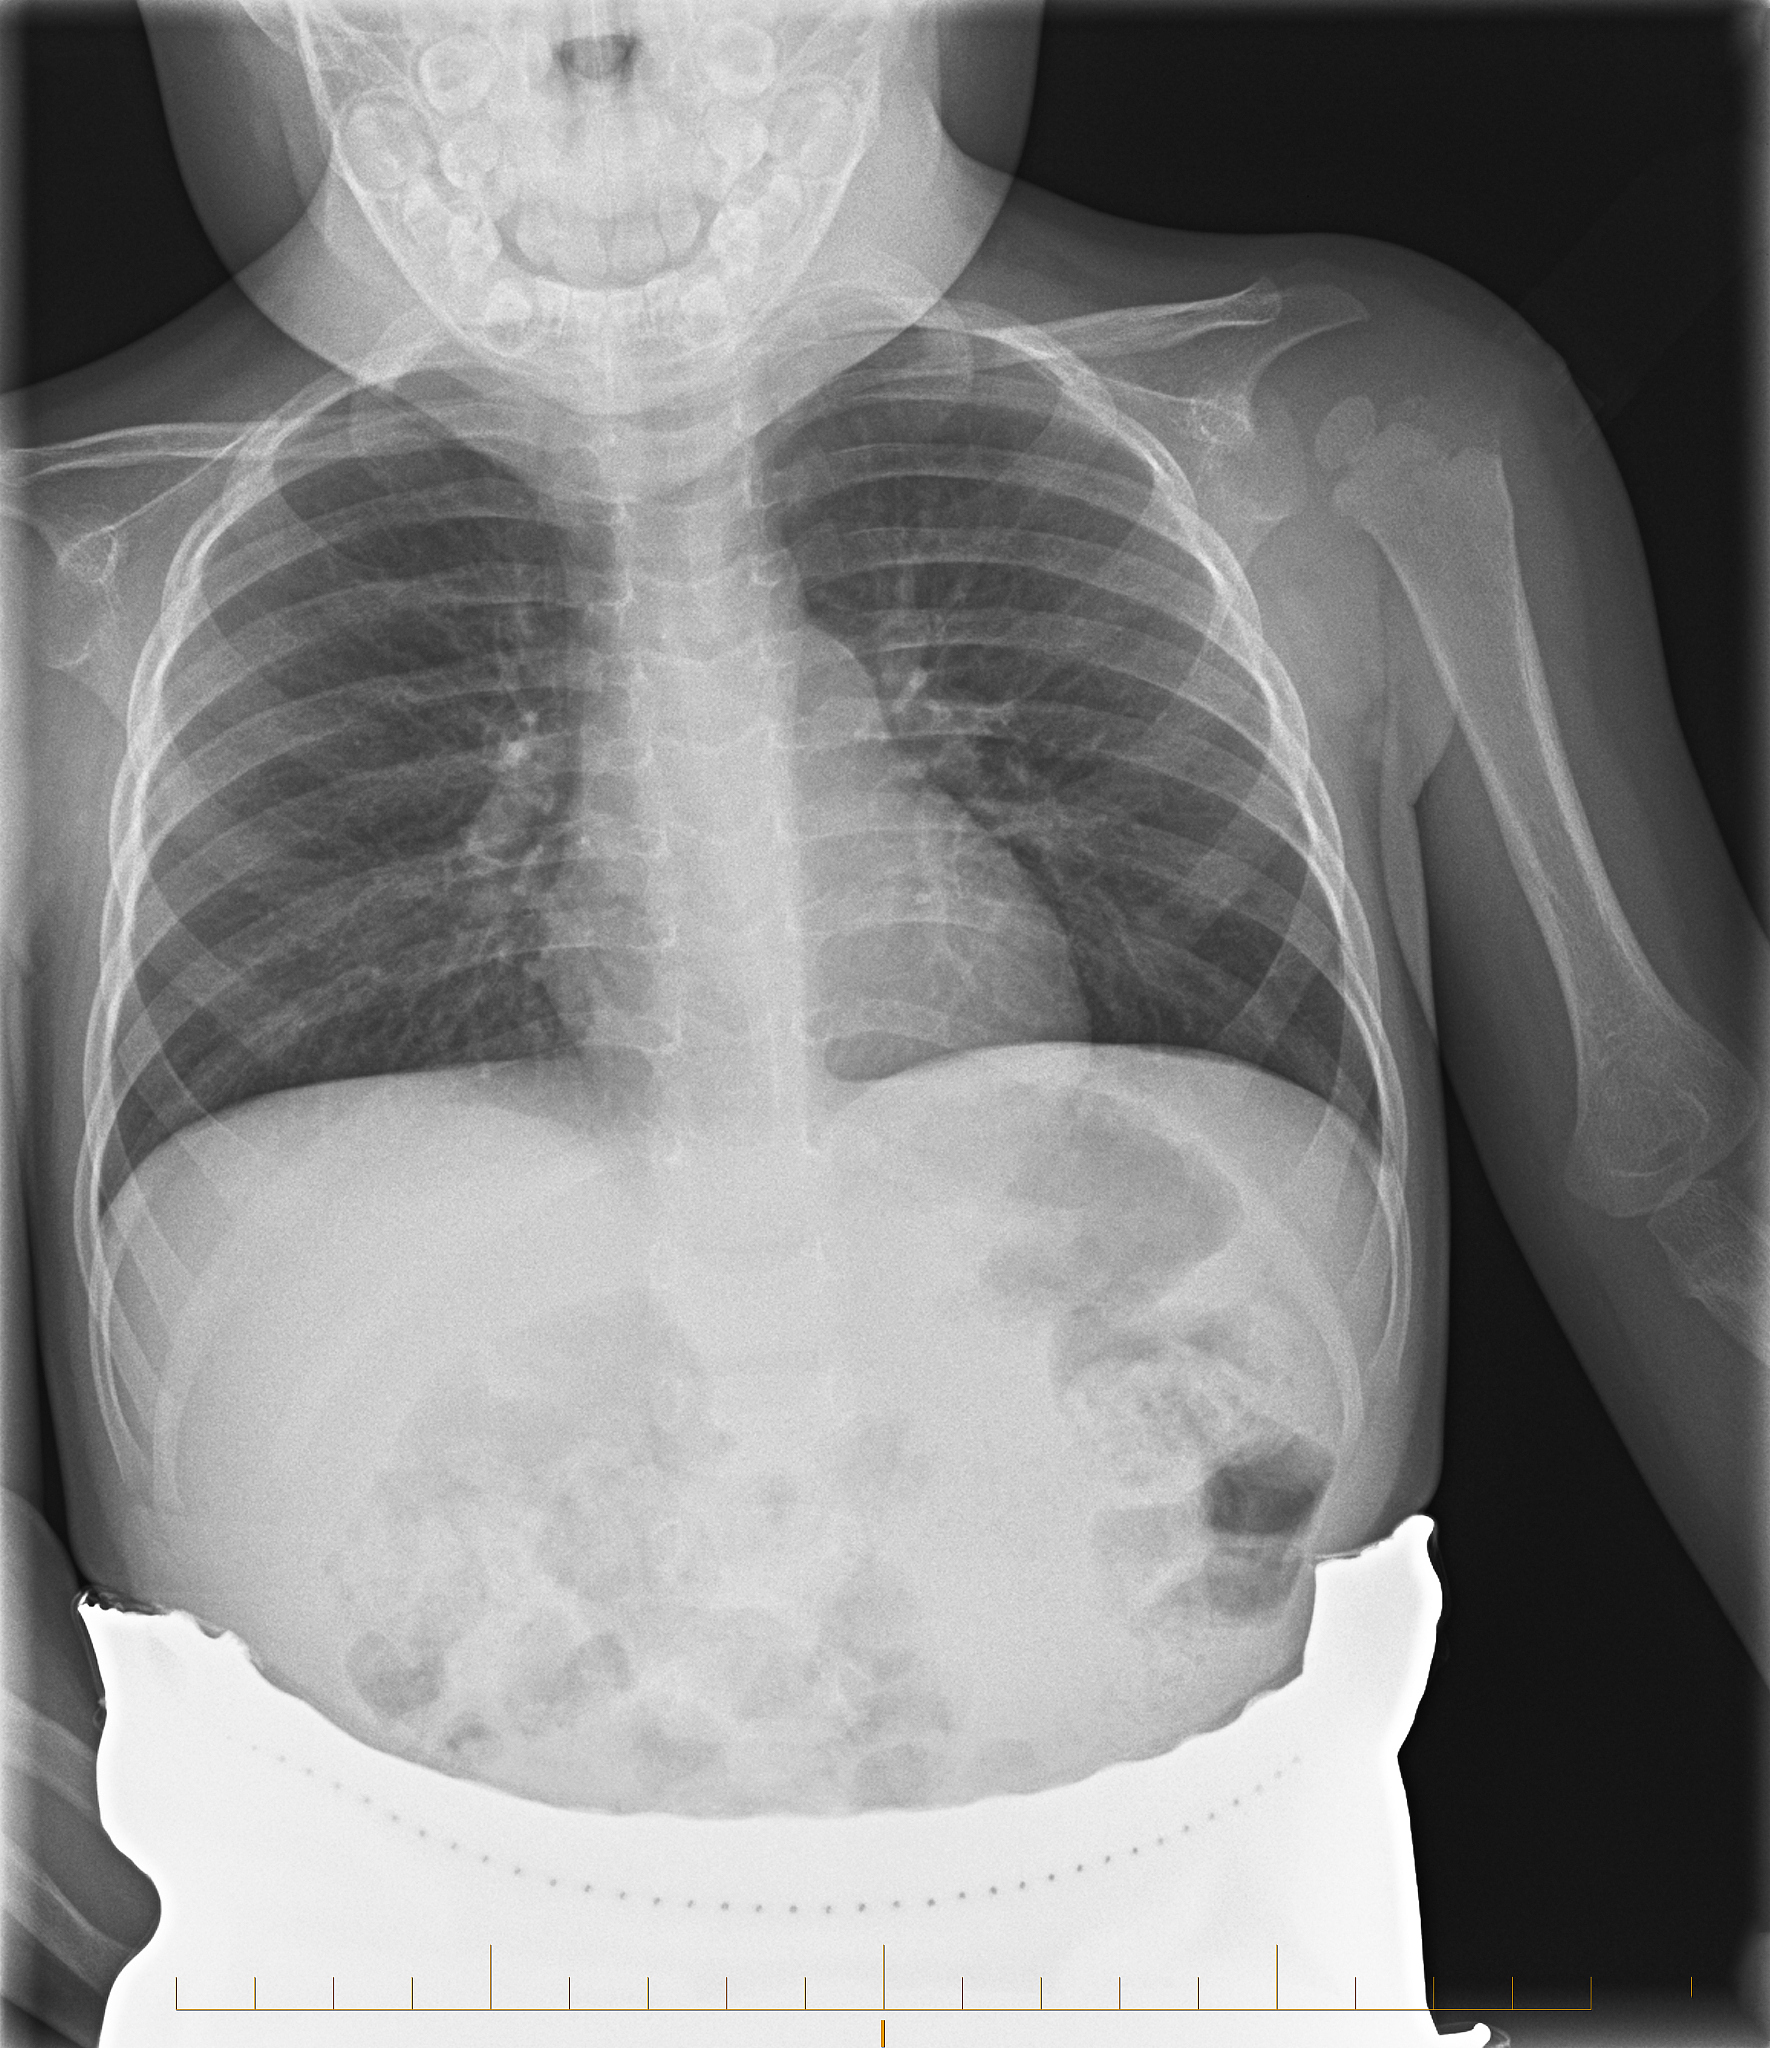

左边肋骨凸起来的原因可能有多种,包括:

1. 胸廓畸形:例如胸骨前突、胸骨后凸等,导致肋骨在某个部位凸起。

2. 骨折或骨裂:肋骨骨折或骨裂后可能出现凸起。

3. 肿瘤:肋骨周围的肿瘤或肿瘤转移也可能导致肋骨凸起。

4. 骨髓增生症:骨髓增生症是一种骨髓细胞异常增生的疾病,可能导致骨骼畸形和肋骨凸起。

5. 骨质增生症:骨质增生症是一种骨骼疾病,可能导致骨骼增生和肋骨凸起。

如果出现左边肋骨凸起的情况,建议及时就医,进行相关检查,以确定具体的病因,并进行相应的治疗。